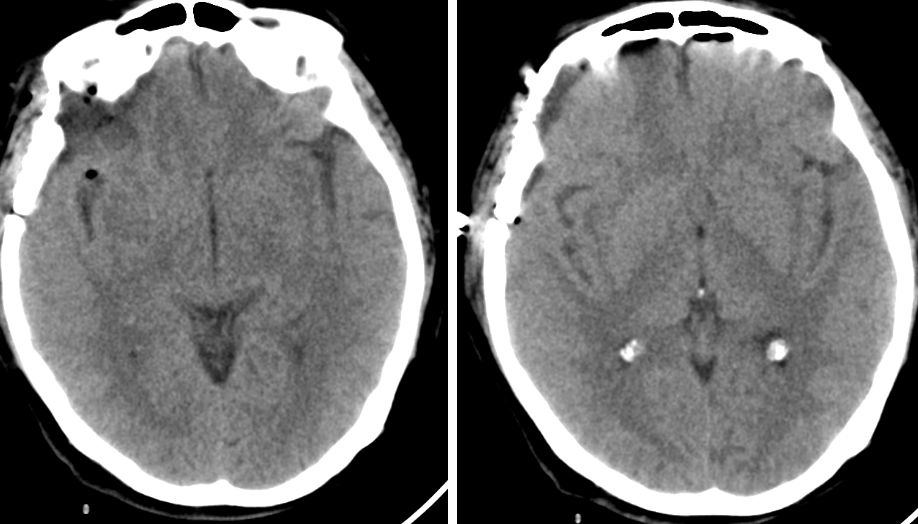

患者约2个月前无明显诱因(否认外伤史)间断出现头痛,头痛为胀痛,左侧较明显,恶心未吐,食欲、睡眠尚可,未予特殊诊治,1个月前患者头痛逐渐加重,思睡,反应略迟钝,行头部CT检查示“慢性硬膜下血肿(双侧)”,于2018年12月15日行颅骨钻孔引流术(左)。术后9天患者恢复良好出院。出院后2周于2019年1月9日患者头痛再次加重,伴有反应迟钝,走路困难,疲乏无力再次就诊,头部CT示“慢性硬膜下血肿(右侧)”,当日再次行颅骨钻孔引流术(右)。术后患者一般状态逐渐好转,无抽搐,无尿便失禁。

2018年12月14日第一次入院

自诉偶有头痛,生活自理。查:神志清,反应迟钝,少语,血压160/95mmHg,颈软,右侧肌力IV级。

2018年12月16日术后第一日

自诉头痛明显缓解。查:神清语明,血压145/85mmHg,颈软,四肢肌力V级。

2018年12月24日出院当日

自诉偶有头痛,生活自理。查:神清语明,血压135/85mmHg,颈软,四肢肌力V级。

2019年1月9日第二次入院

近3天头痛明显,生活严重受限。有过尿失禁。查:神志清,反应迟钝,走路不稳,血压160/95mmHg,颈软,左侧肌力III级。